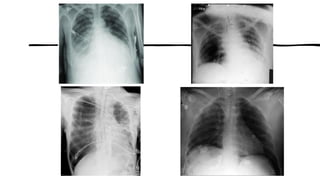

POSICIONAMENTOS DE ROTINA - TÓRAX

• INDICAÇÕES CLÍNICAS (P/ Posição Ortostática)

• •Derrames pleurais

• •Pneumotórax

• •Atelectasia e sinais de infecção.

• ROTINA BÁSICA TÓRAX

• •PA (Posteroanterior)

• •Perfil Esquerdo